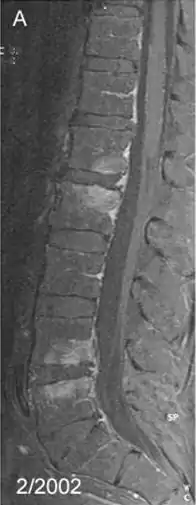

Спондилит — воспалительное заболевание позвоночника. Является одной из форм спондилопатии. При спондилите происходит первичное разрушение тел позвонков, что приводит к деформации позвоночника.

Спондилит, вызванный Tropheryma whipplei